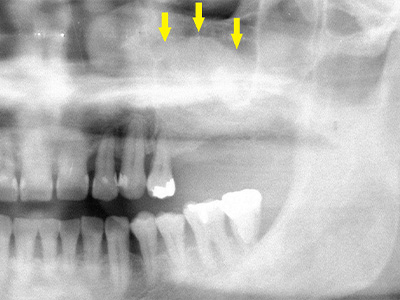

患者様の智歯の辺りから、患者様ご自身の骨を採取し、移植した後のレントゲン写真です。

採取した骨片を、小さなチタン製のスクリューで固定してあります。

これが遊離自家骨移植術です。 -